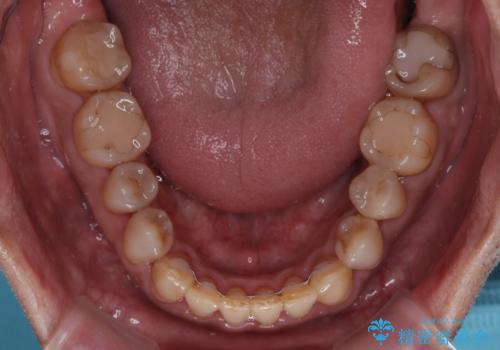

- 前歯のクロスバイトを気にして来院された患者様です。

下顎骨の左右のずれがあり、下顎全体が前方に出ている状態であったので、無理をせずにワイヤー装置にて矯正治療を行うこととしました。

クロスバイト改善には難儀しましたが、咬みやすく、笑ったときに清潔感ある口元に仕上げることができました。